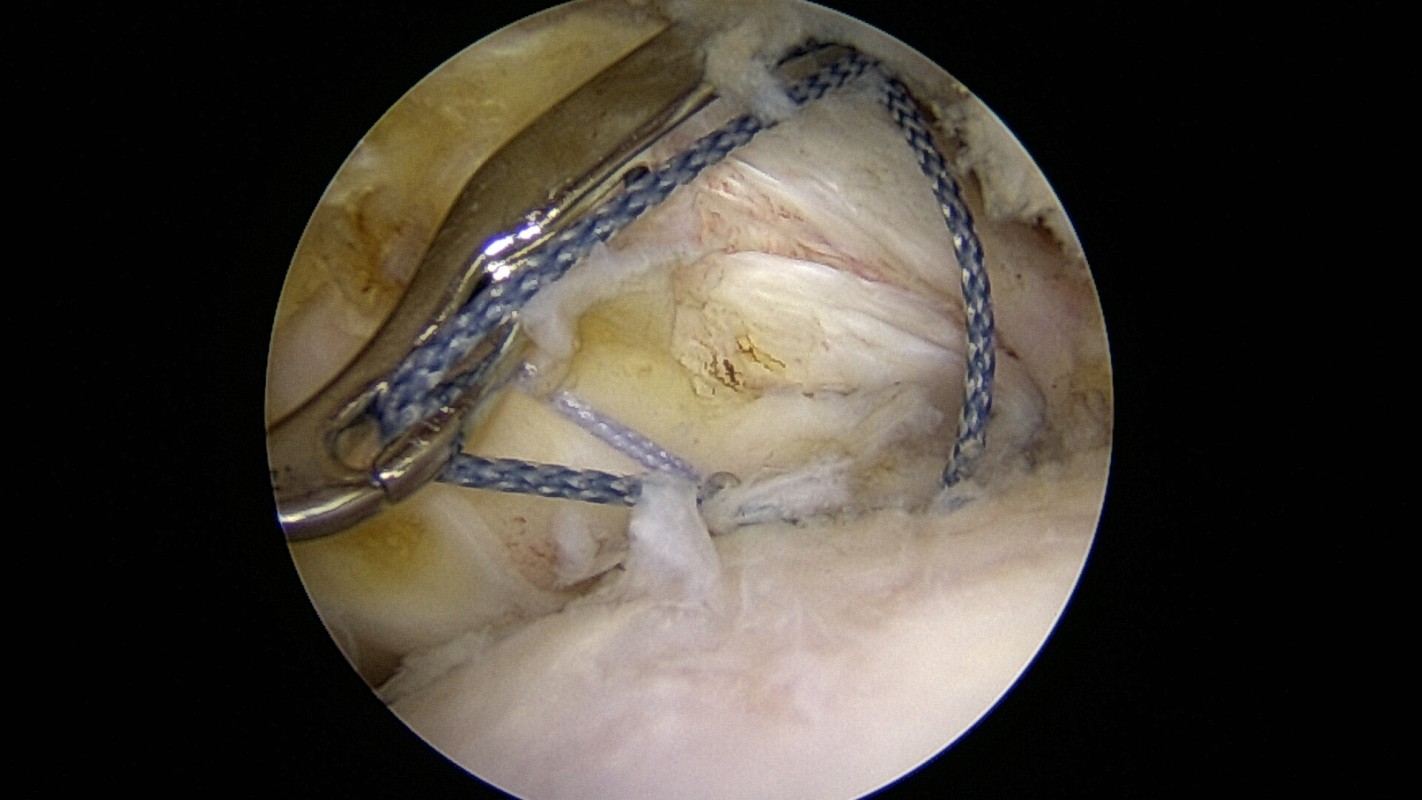

La faisabilité de cette réparation est évaluée par IRM ou athro-scanner, mais des imprévus quand à la qualité tendineuse rencontrée durant l’intervention sont possibles : l’intervention planifiée peut donc différer de celle effectivement réalisée ! De petites vis (en titane ou résorbables) munies de fils sont introduite dans l’os de l’humérus. Des passe-fils miniaturisés permettent de fixer le tendon à l’os.

Réparation de tendon: récupération des fils